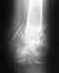

Здравствуйте. У меня оскольчатый винтообразный перелом голени. Сделано вытяжение, поставлен апп.Илизарова. Через 1,5 мес. на снимке трещина, сделана подтяжка спицы, снимок назначен через месяц. Если сопоставление полностью не произошло, возможно ли его будет исправить через месяц? Заранее, спасибо.